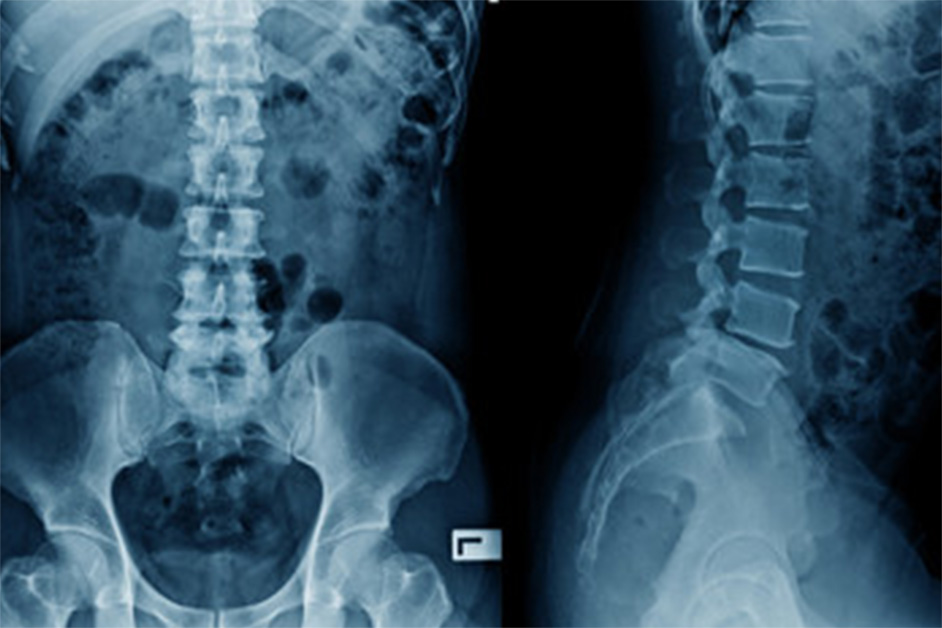

2. レントゲン検査

レントゲン検査

骨の変化の程度や骨折の有無、腫瘍が疑われる所見がないかを確認します。あわせて、骨粗しょう症に関連する変化がみられないかも確認します。

骨粗しょう症による骨折が起こりやすいとされる腰椎や大腿骨近位部(脚のつけ根)の骨密度を測定できる点が特徴です。